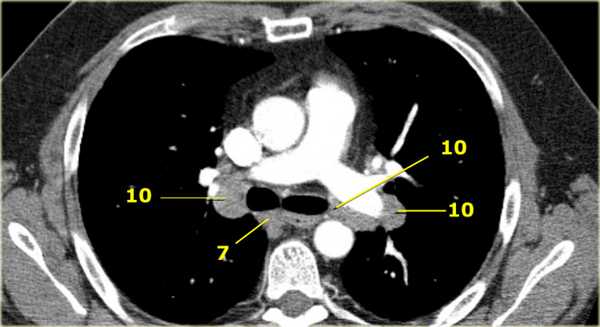

На ниже представленном постконтрастном КТ снимке представлен пациент с карциномой языка и лимфаденопатией II группы лимфатических узлов.

На ниже представленном постконтрастном КТ изображении визуализируется увеличение и контрастное усиление лимфатических узлов III группы.